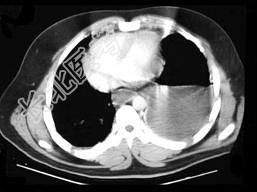

- 单项选择题35岁,男, 因车祸入院,呼吸困难、发绀、上腹痛, 请结合胸片和CT选择最可能的诊断 ( )

A、膈疝

B、胸腔积液

C、膈膨升

D、膈麻痹

E、液气胸